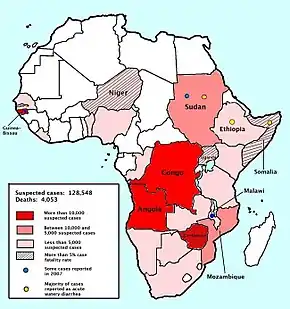

Cholera affects an estimated 2.8 million people worldwide, and causes approximately 95,000 deaths a year (uncertainty range: 21,000–143,000) as of 2015.[84][85] This occurs mainly in the developing world.[86]

In the early 1980s, death rates are believed to have still been higher than three million a year.[17] It is difficult to calculate exact numbers of cases, as many go unreported due to concerns that an outbreak may have a negative impact on the tourism of a country.[38] As of 2004, cholera remained both epidemic and endemic in many areas of the world.[17]

Recent major outbreaks are the 2010s Haiti cholera outbreak and the 2016–2022 Yemen cholera outbreak. In October 2016, an outbreak of cholera began in war-ravaged Yemen.[87] WHO called it "the worst cholera outbreak in the world".[88] In 2019, 93% of the reported 923,037 cholera cases were from Yemen (with 1911 deaths reported).[89] Between September 2019 and September 2020, a global total of over 450,000 cases and over 900 deaths was reported; however, the accuracy of these numbers suffer from over-reporting from countries that report suspected cases (and not laboratory confirmed cases), as well as under-reporting from countries that do not report official cases (such as Bangladesh, India and Philippines).[89]

Cholera had disappeared from the Americas for most of the 20th century, but it reappeared toward the end of that century, beginning with a severe outbreak in Peru.[90] This was followed by the 2010s Haiti cholera outbreak[91] and another outbreak of cholera in Haiti amid the 2018–2023 Haitian crisis.[92] As of August 2021 the disease is endemic in Africa and some areas of eastern and western Asia (Bangladesh, India and Yemen).[91] Cholera is not endemic in Europe; all reported cases had a travel history to endemic areas.[91]